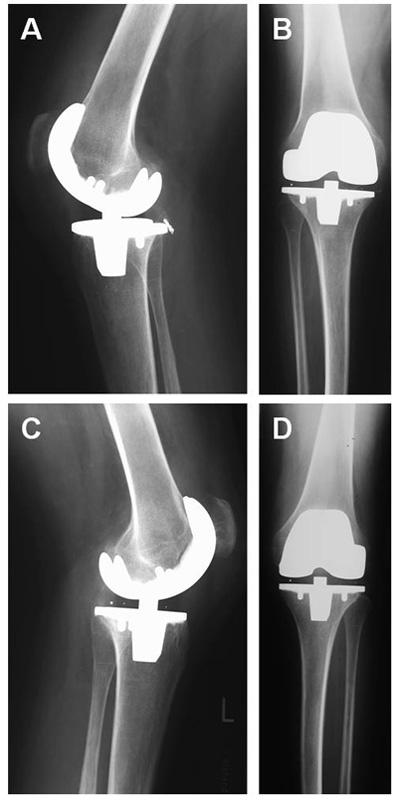

Figure 4

One year postoperative x-rays of both knees. Correct anatomic position of the prostheses, no signs of loosening. (a) Right knee lateral view (b) Right knee anterior-posterior view (c) Left knee lateral view (d) Left knee anterior-posterior view.

Thereafter the patient could be mobilised with crutches and left the hospital on day 26. One year after the operation the patient reached a bilateral flexion of 90° passively and up to 80° actively with a persistent extension deficit of 5°. He was able to walk continuously without assistance for up to three hours, and rising from a chair posed no further problem. X-rays showed no signs of loosening (fig. 4).

Some authors report a fair gain in range of motion postoperatively in haemophilic arthropathy [17, 18]. In the case presented the extensive debridement and release, especially of the posterior knee compartment, resulted in an intraoperative range of motion of flexion/extension 80/5/0° with soft endpoints. Due to an intensive postoperative rehabilitation programme this range of motion could be maintained and remained the same for one year after surgery. The lasting gain in range of motion was impressive considering the preoperative fixed flexion deformity of 20°.